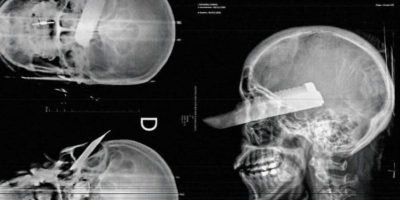

A mulher conseguiu correr para a rua, mas foi alcançada. Nesse momento, o agressor sacou uma faca e cravou no rosto dela, atingindo diretamente o olho direito. Mesmo ferida, a vítima conseguiu se abrigar na casa de um vizinho. O agressor ainda foi até o local, pediu desculpas e fugiu.

O Corpo de Bombeiros prestou os primeiros socorros e levou a mulher ao Hospital Padre João Berthier. Conforme o médico que a atendeu, a vítima não corre risco de morte, mas vai perder a visão do olho atingido. Ela também apresentava hematomas por todo o corpo.